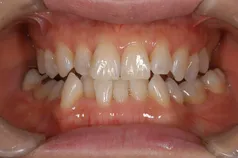

[症例]

矯正治療を行っています。

治療前は上下の歯が反対になっている所もあり、上の歯の真ん中から2本目の歯は矮小歯と言って、平均より小さな歯のため上唇が引っ込んで見えます。

インビザラインでマウスピース矯正後、オフィスホワイトニングを行い、矮小歯はラミネートベニアで修復しました。

綺麗な歯並びになるとともに、上顎の歯列のアーチが広がって、上唇がやや前方に出ることで自然な口元になりました。

[費用・期間・副作用]

- 治療期間: 1年6ヶ月

- 治療回数: 10回

- 費用: 120万円

- デメリット:治療後に矯正の後戻り防止のためのマウスピースを使用しなければならない